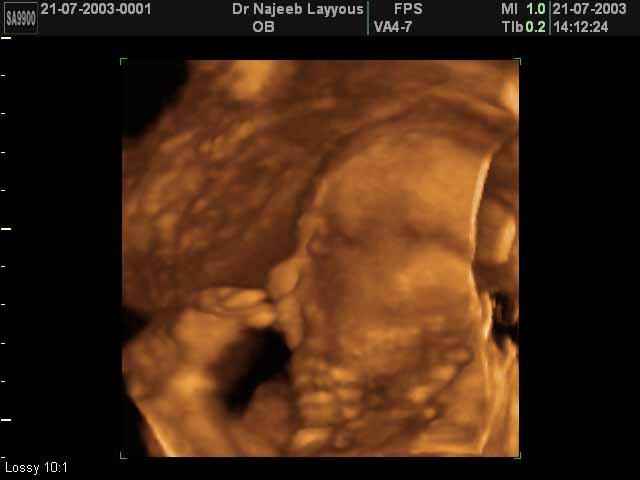

- صور جانبية لرأس الجنين

صور جانبية لرأس الجنين بجهاز الالتراساوند ثلاثي الأبعاد | الدكتور نجيب ليوس